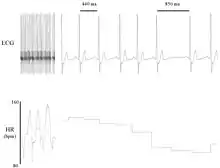

Heart rate variability (HRV) is the physiological phenomenon of variation in the time interval between heartbeats. It is measured by the variation in the beat-to-beat.

Other terms used include "cycle length variability", "R–R variability" (where R is a point corresponding to the peak of the QRS complex of the ECG wave; and RR is the interval between successive Rs), and "heart period variability".

Variation in the beat-to-beat interval is a physiological phenomenon. The SA node receives several different inputs and the instantaneous heart rate or RR interval and its variation are the results of these inputs.

The main inputs are the sympathetic and the parasympathetic nervous system (PSNS) and humoral factors. Respiration gives rise to waves in heart rate mediated primarily via the PSNS, and it is thought that the lag in the baroreceptor feedback loop may give rise to 10 second waves in heart rate (associated with Mayer waves of blood pressure), but this remains controversial.